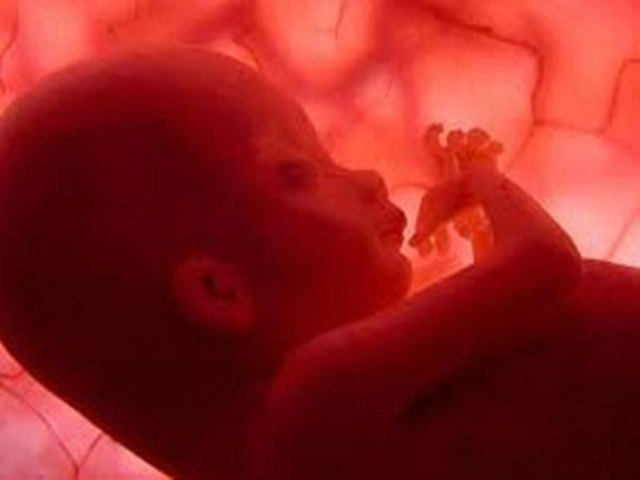

El embrión a formado todos los órganos. Las extremidades ya están formadas. El embrión se mueve y disfruta de todo su espacio dentro del saco amniótico.

Mide 5,5 cm y pesa 9 g. Poco a poco, su cabeza está más erguida y va tomando forma redondeada.

Los ojos, cubiertos por unos finísimos párpados, se van situando en la parte delantera de la cara y sus orejas avanzan hacia su ubicación definitiva.

Las fosas nasales están todavía bastante separadas.

Las cuerdas vocales hacen su aparición.